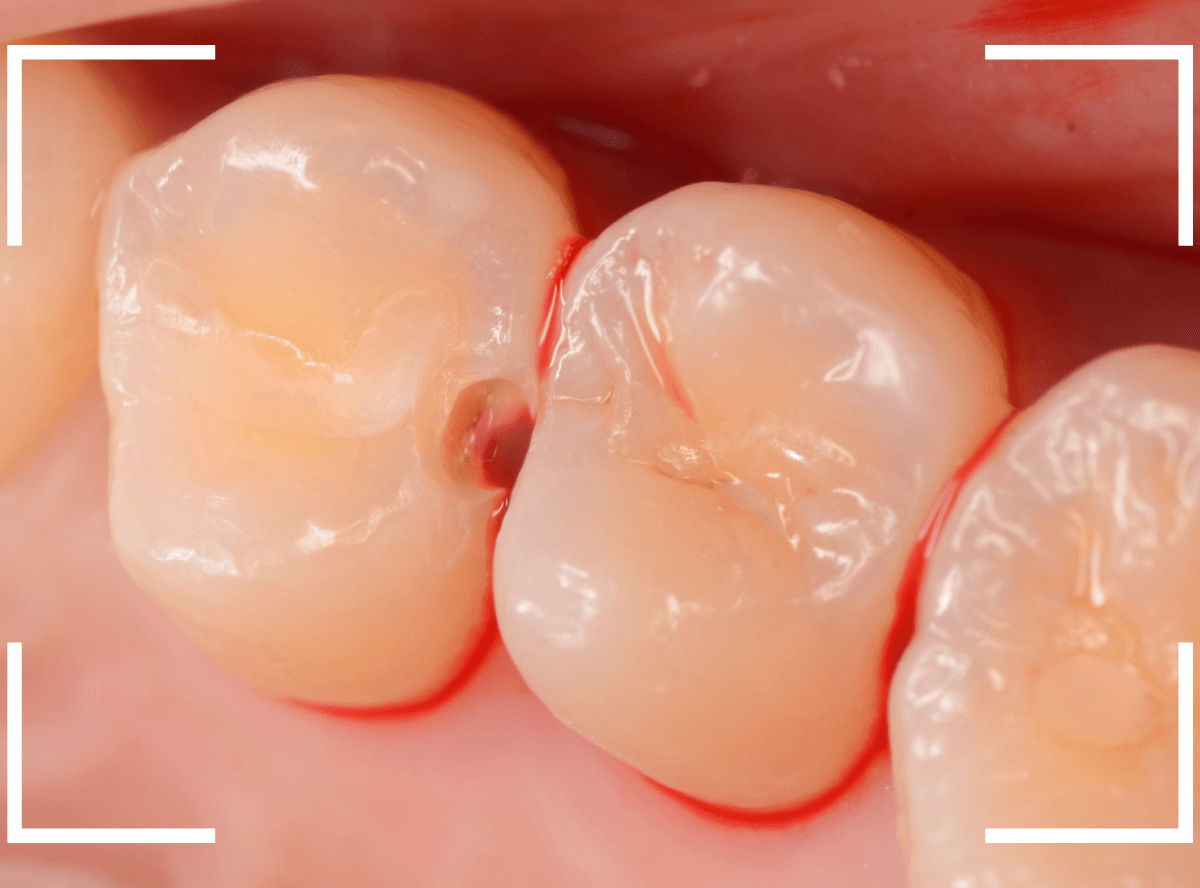

特に症状はありませんが、歯の咬頭(噛み合わせの山の部分)に小さな穴が空いていて、その周りがもやっと黒く見え、虫歯が怪しいです。

レントゲン写真で確認しますが、ここでは特に問題はなさそうに見えます。

患者さんに状況を説明し、慎重に削って調べる事になりました。

少しずつ穴の部分を削ってみると、ズブッと落とし穴にはまるような柔らかい虫歯の層(=軟化象牙質)に当たりました。

慎重に虫歯を除去したところです。

歯の溝のレジンが詰めてあった部分まで虫歯は進行していました。

とはいえ、それほど深く虫歯は進行していませんでしたので、虫歯除去後、レジンを充填して治療は終われました。